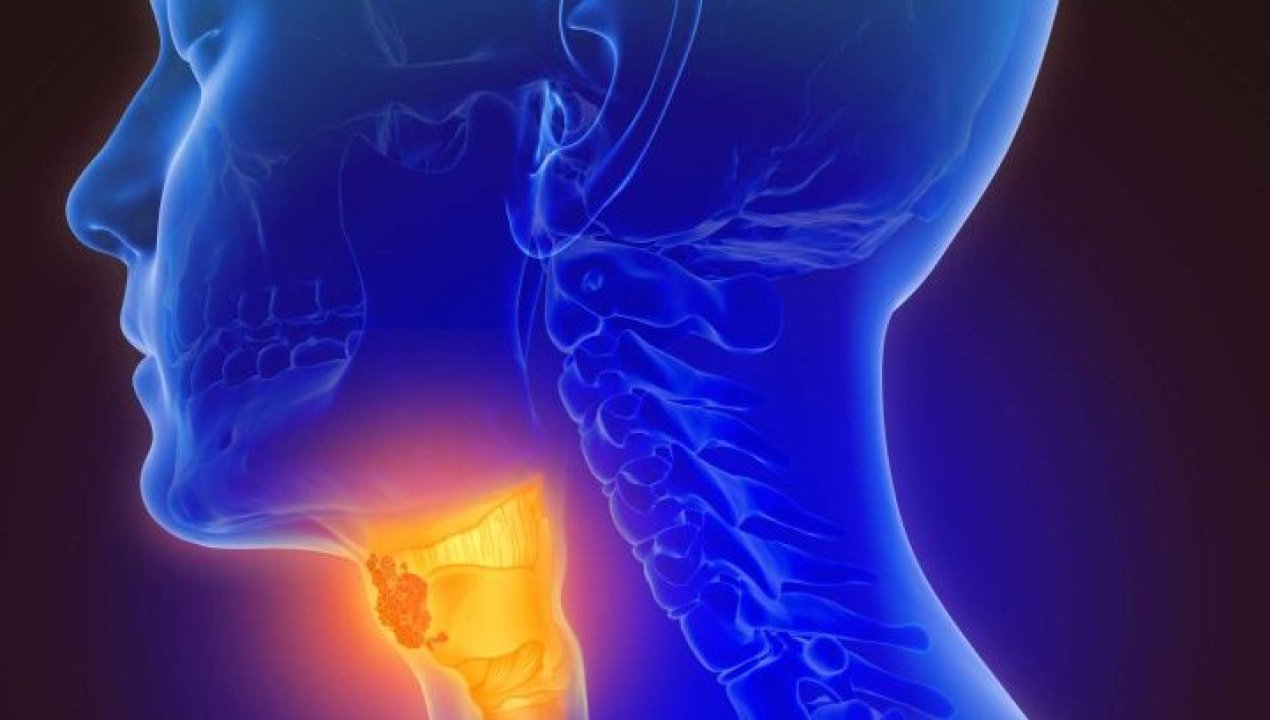

JUNTOS EN TALTAL Y LA REGIÓN: PREVENIMOS EL CÁNCER

El Cáncer en Chile y el mundo